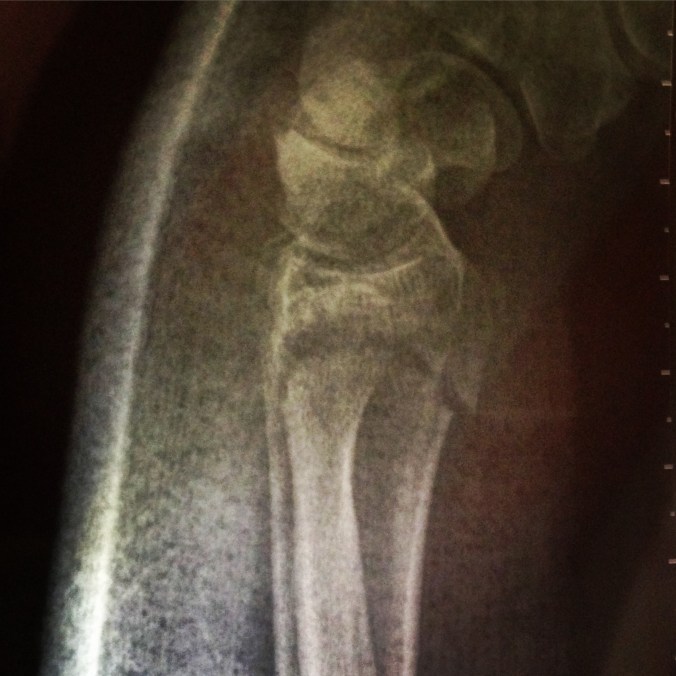

Check out the weird shape the orthopod bent my arm into (and they wondered why my bone had moved from the original setting when the cast came off – sigh)